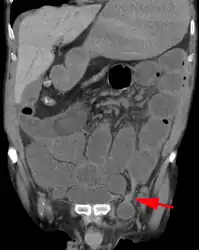

An incarcerated inguinal hernia as seen on cross sectional CT scan -

A frontal view of an incarcerated inguinal hernia (on the patient's left side) with dilated loops of bowel above. -

An inguinal hernia which contains part of the bladder. Bladder cancer also present. -